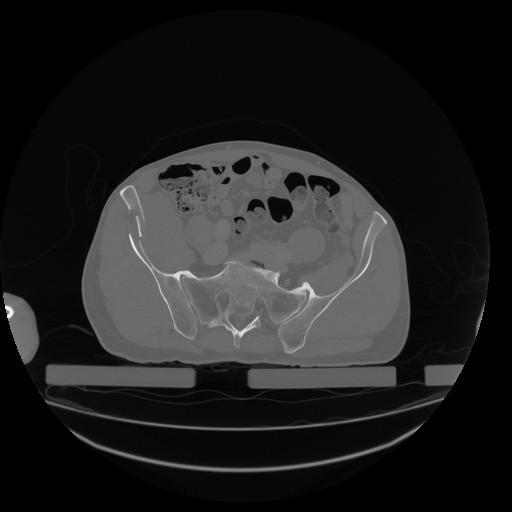

34 CUERPO,CE,Vol,1.0,CUERPO,,